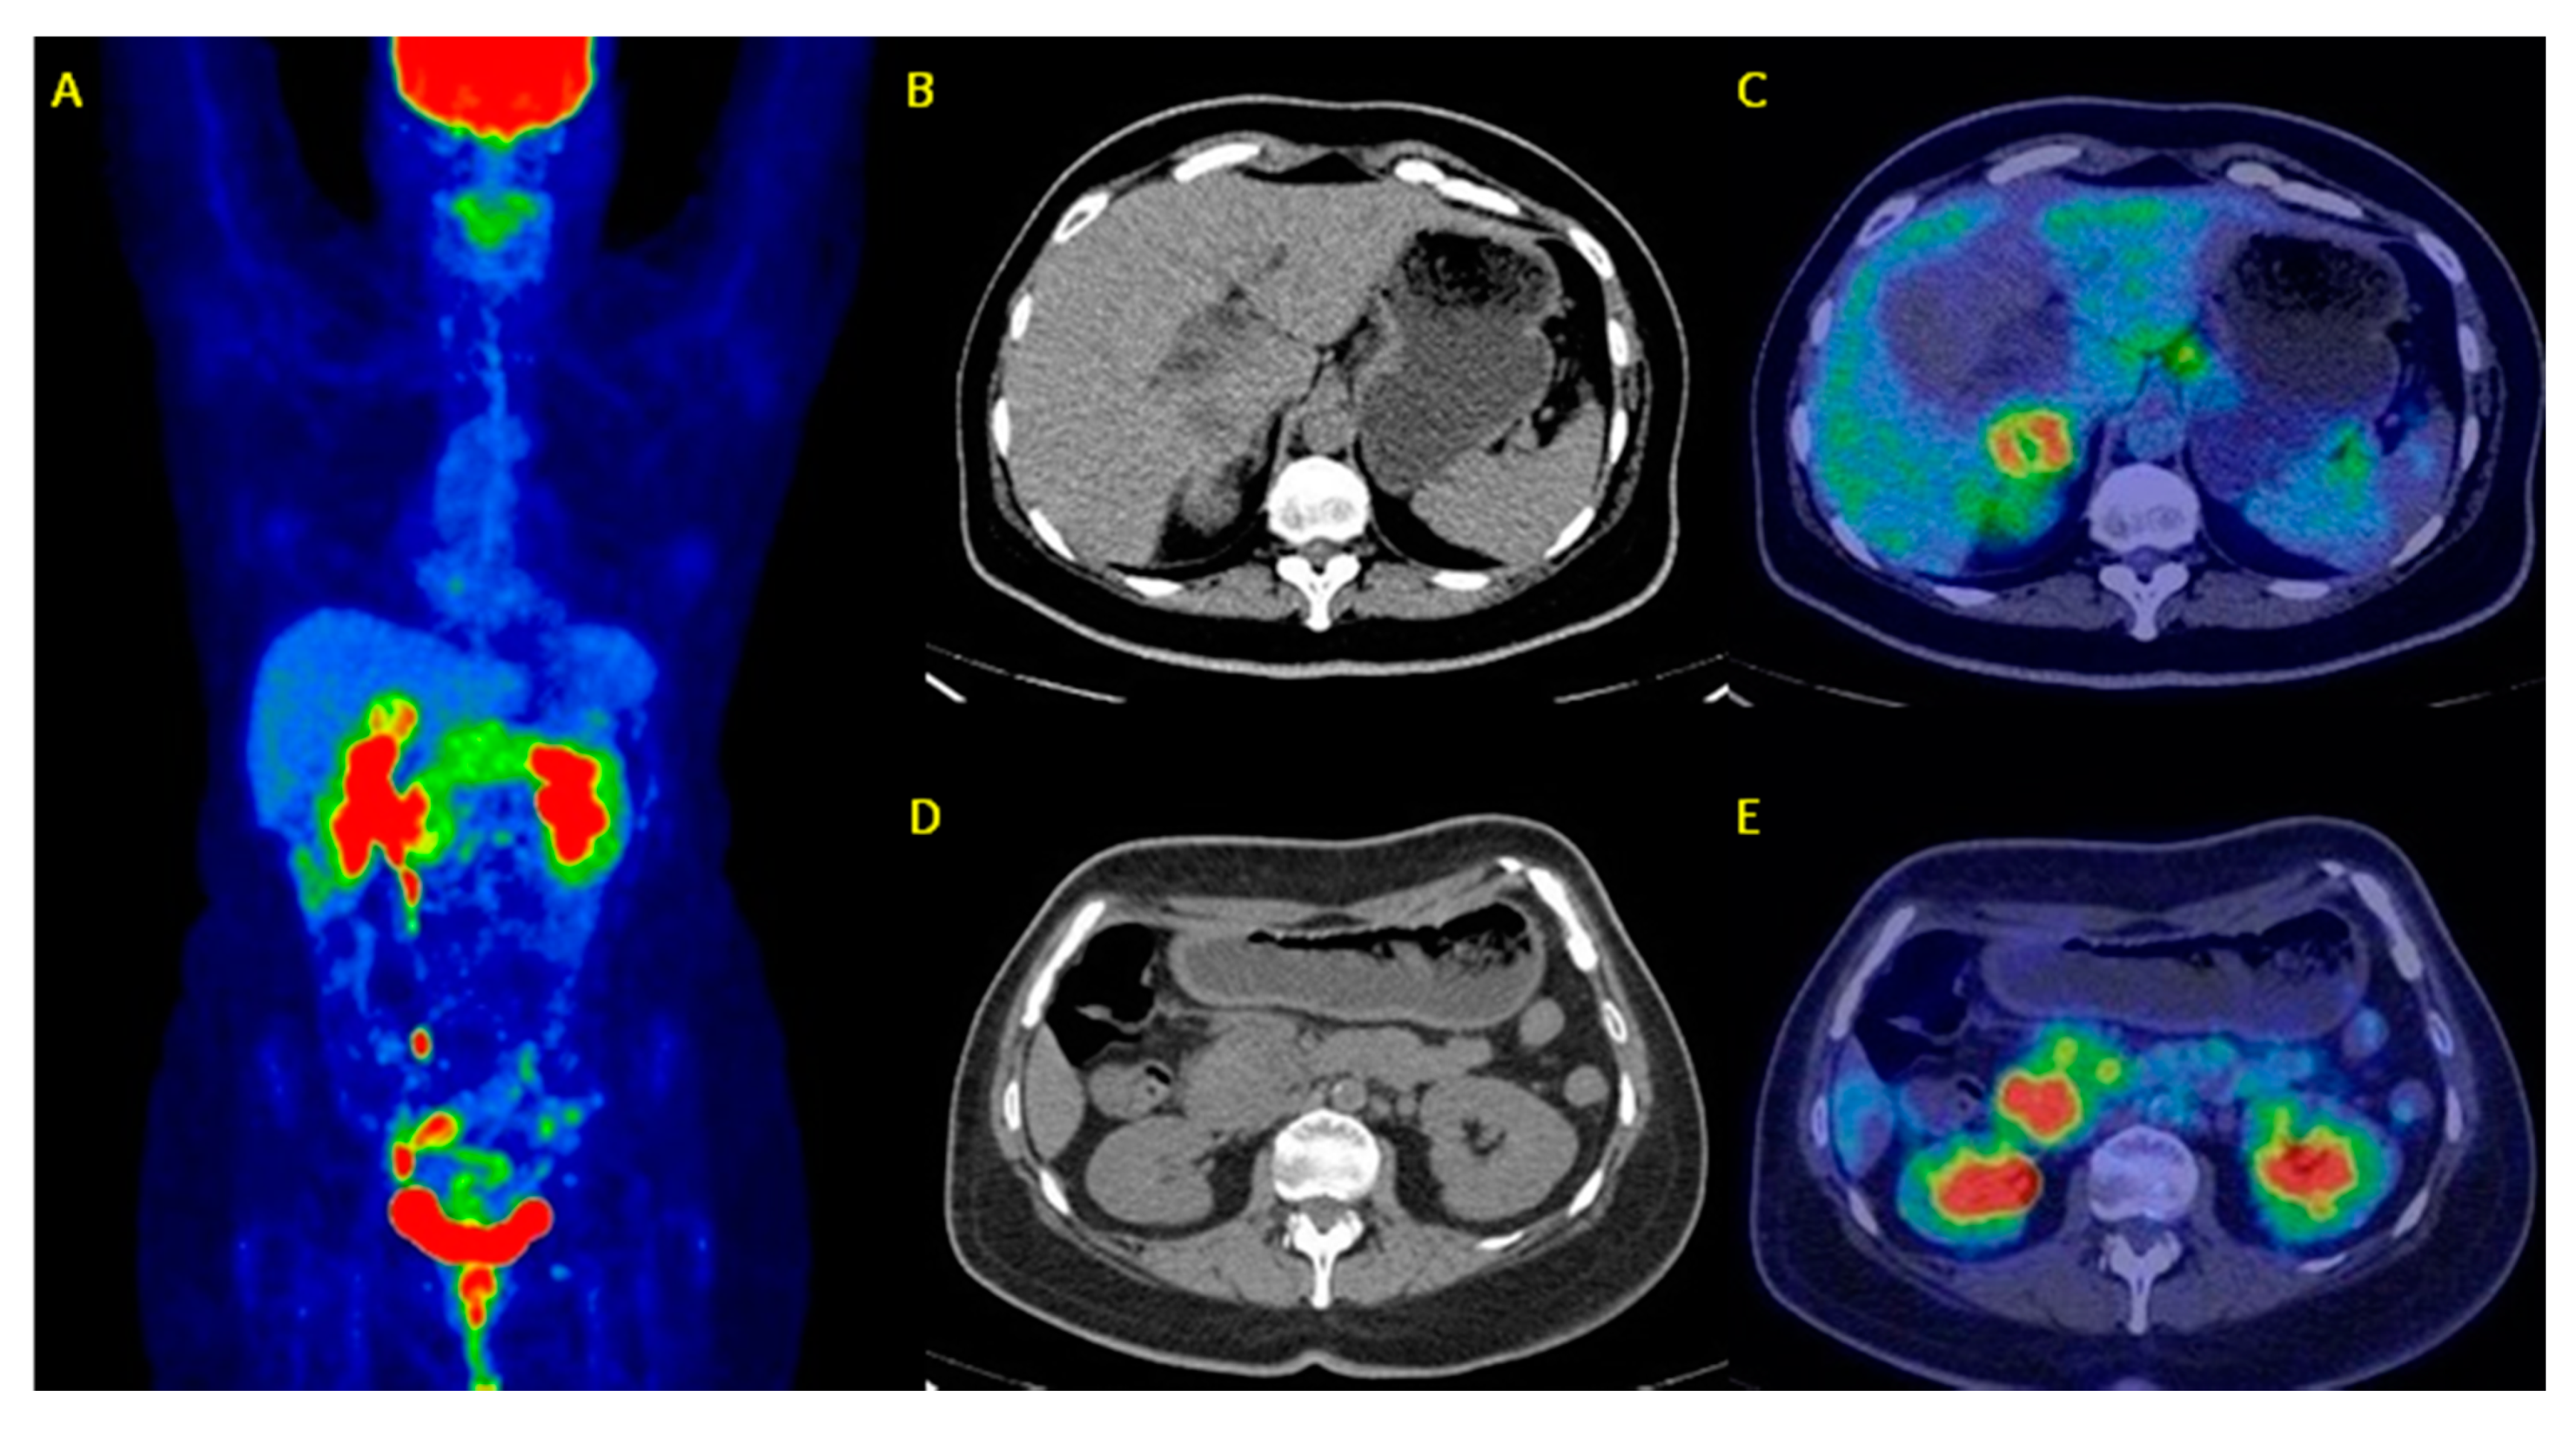

| 18 | Albano et al. [33] | 2018 | Retrospective study | 52 (59 (42–78)) | Restaging 28 surgery, 12 neoadjuvant chemotherapy+surgery+radiotherapy, s6 neoadjuvant chemotherapy+surgery, and 6 chemotherapy | PET/CT has a high diagnostic accuracy in the restaging process and significantly influences the therapeutic management in ∼30% of cases. |